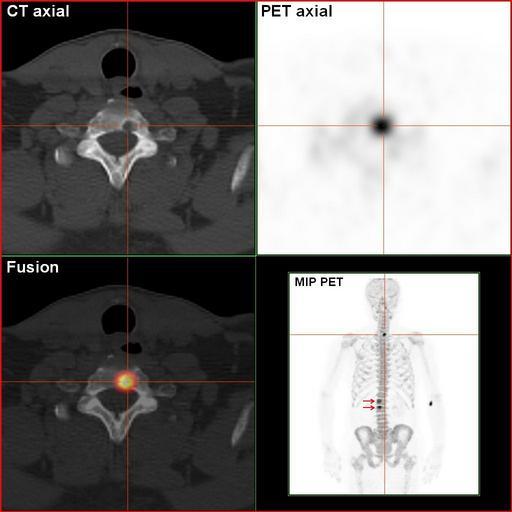

| Keywords: RenalCancer-90MBq-F-18-Fluorid-PET-CT.jpg en Sodium-Fluoride-PET-Scan of a patient suffering from kidney disease with several bone matastases in the vertebral column This is the same patient as shown in the image RenalCancer-700MBq-HDP-BoneScinti-3hpi jpg The osteolytic metastasis in the neck is clearly visible de Natriumfluorid-PET/CT-Scan eines Patienten mit metastasiertem Nierenkarzinom Dies ist der selbe Patient wie im Bild RenalCancer-700MBq-HDP-BoneScinti-3hpi jpg Die osteolytische Knochenmetastase in der Halswirbelsäule ist klar dargestellt own Hg6996 2011-03-14 Mit freundlicher Genehmigung Südwestdeutsches PET-Zentrum Stuttgart am Diakonie-Klinikum Stuttgart Cc-zero Positron emission tomography | ||||